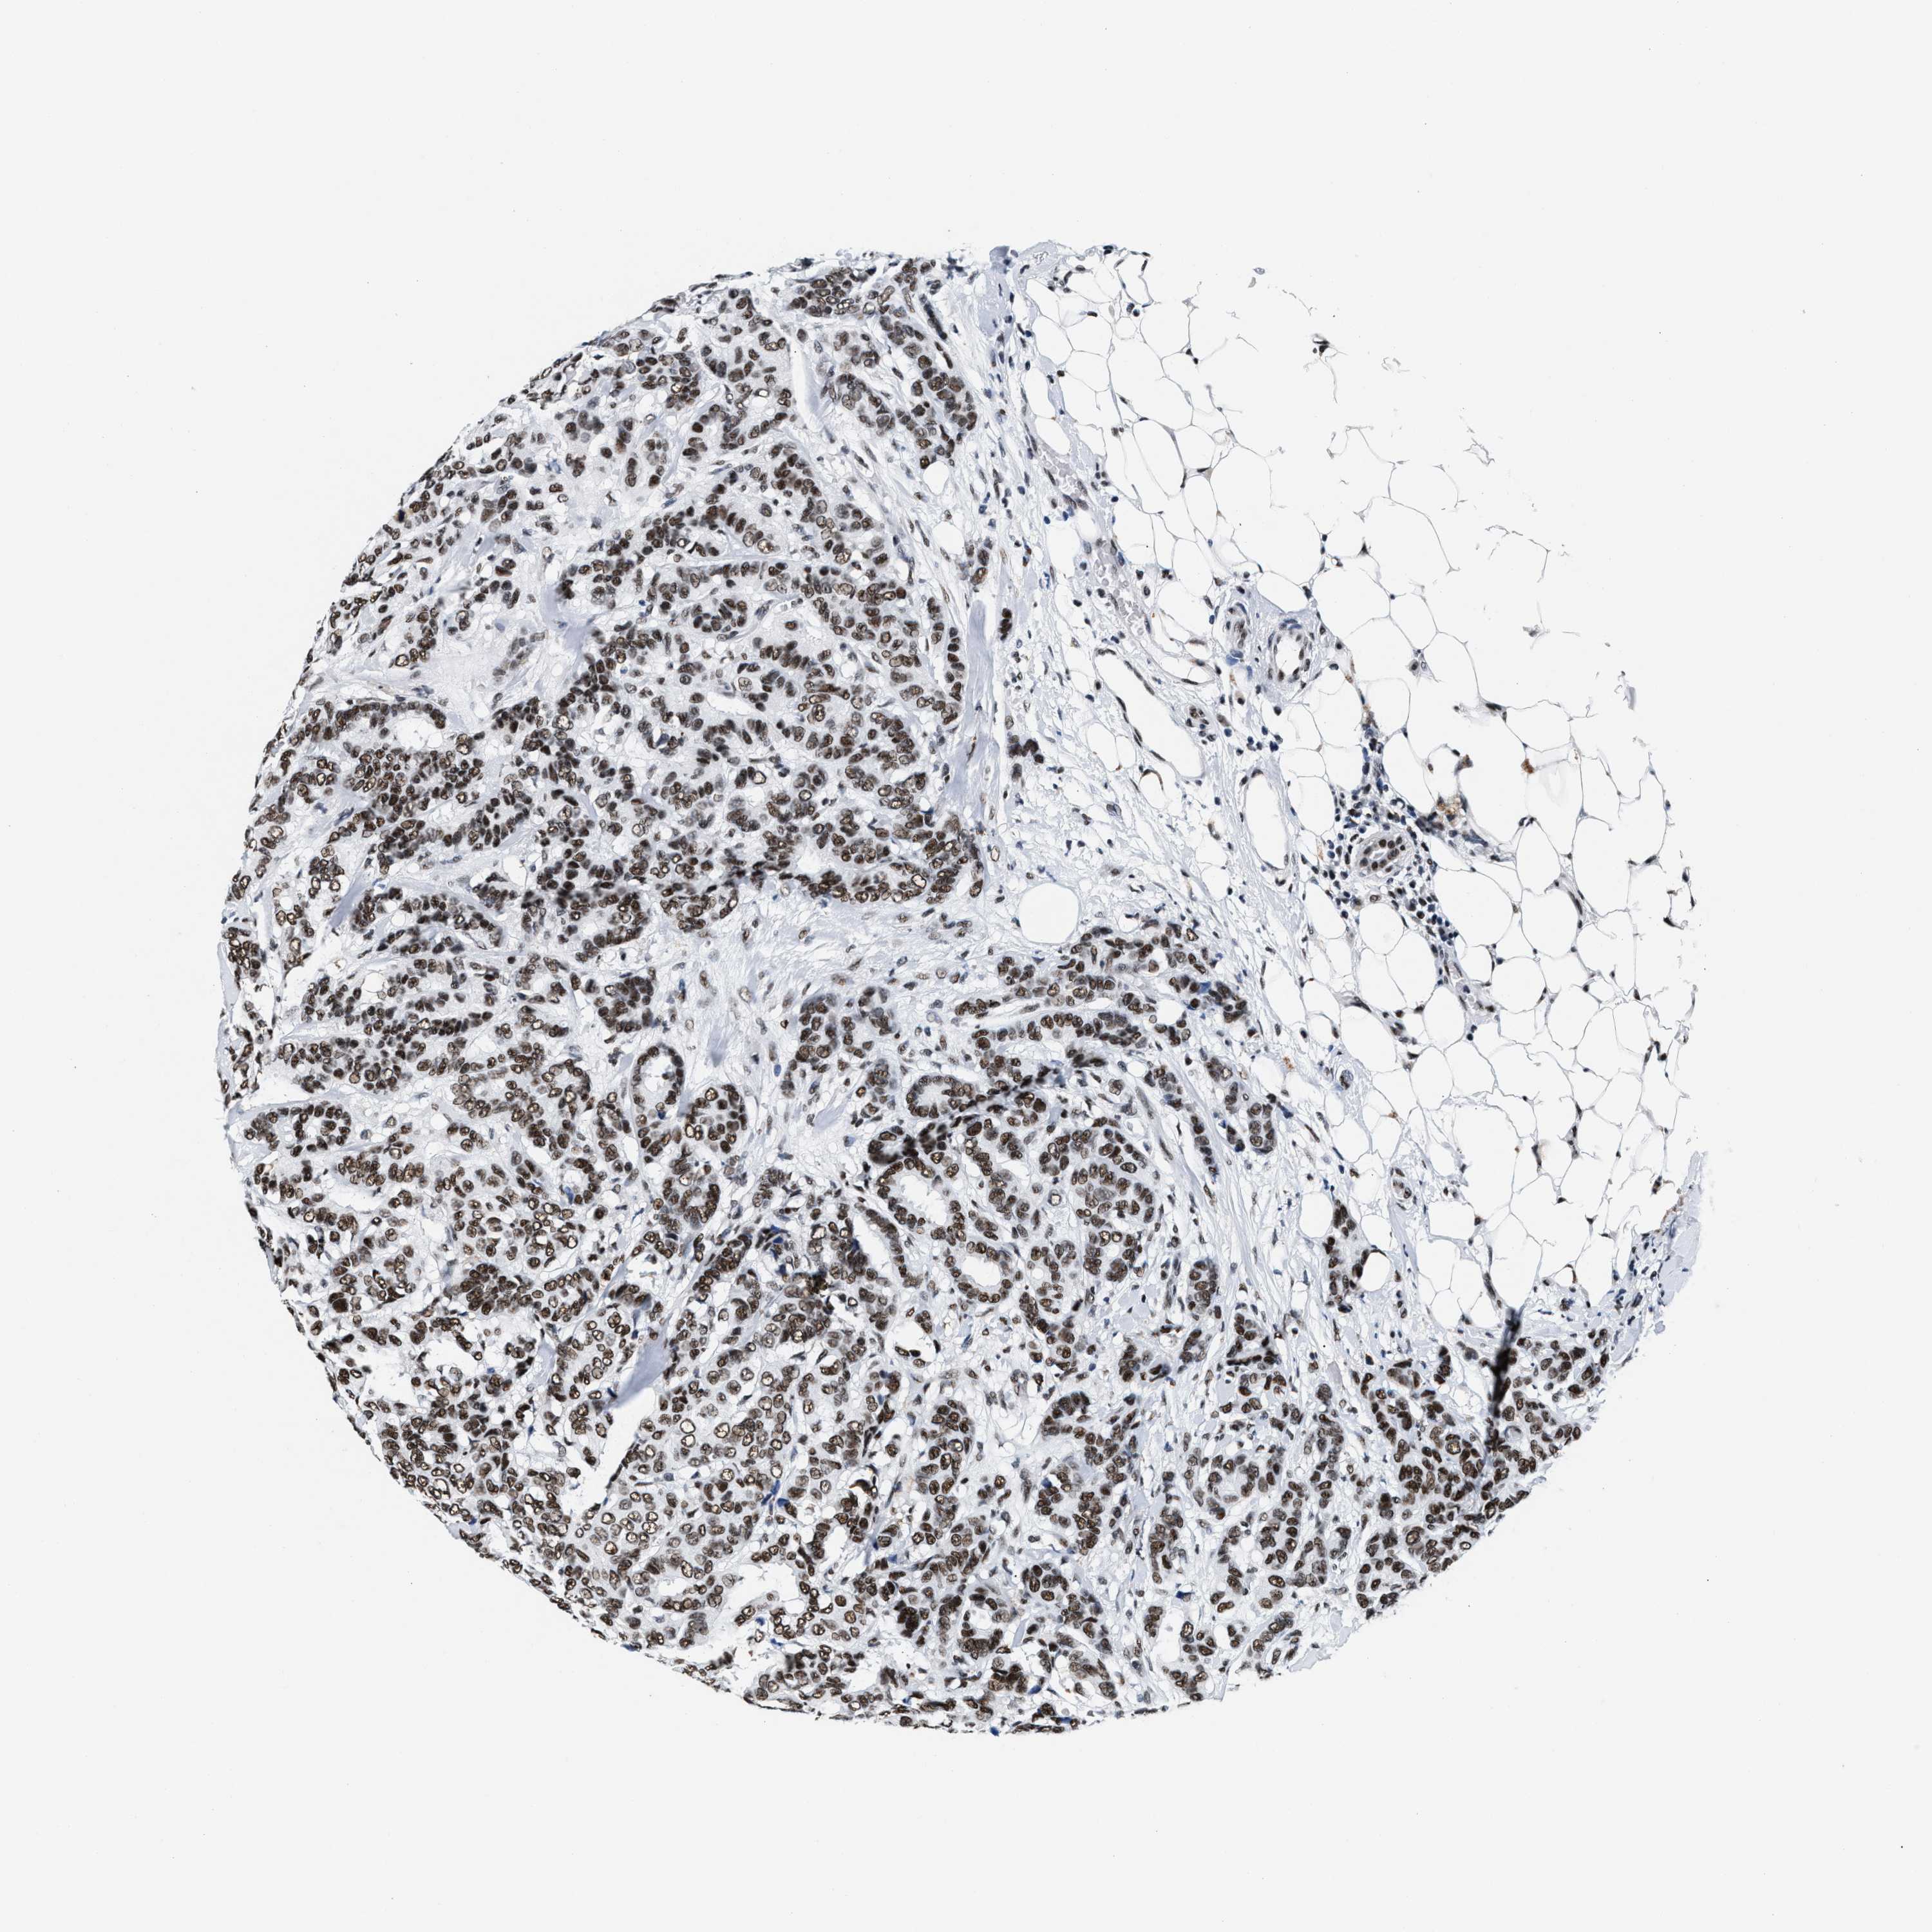

BRCA TCGA BRCA VALIDATION PROTEIN EXPRESSION